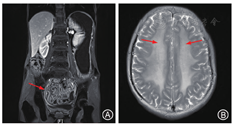

影像学检查:小肠MRI示结肠回盲部、下腹回肠肠管管壁呈较广泛不同程度肿胀、增厚(图1A),考虑为炎性改变;胆汁淤积;胃呈无力型改变。颅脑MRI示中脑、脑桥、双侧小脑半球及双侧丘脑、基底节区、半卵圆中心弥漫性片状较对称异常信号影;双侧筛窦炎,左侧蝶窦内结节状影,性质良性,黏膜囊肿可能(图1B)。